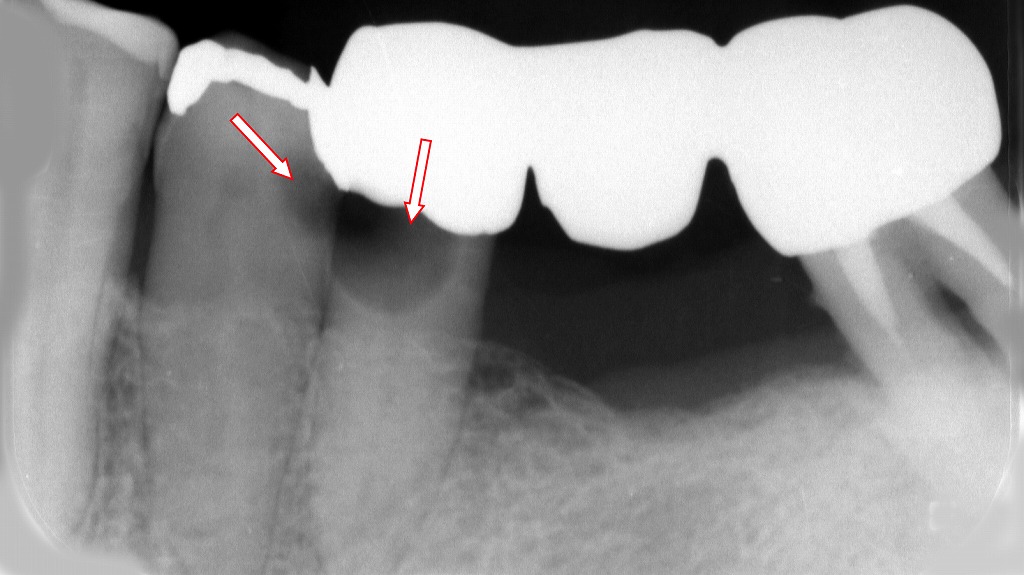

この画像は下顎臼歯部のデンタルX線写真です。赤い矢印の位置に病変が確認されます。以下に詳細を解説します。

🔹全体の状態

- 下顎5番・6番・7番に、金属製の保険適用メタルブリッジが装着されています。

ブリッジとは、欠損した歯(この場合は6番の欠損)を両隣の歯で支える固定式の補綴物です。

🔹5番(右側の矢印)

- ブリッジの支台歯(クラウンがかぶさっている歯)の内部、歯冠の下部に**透過像(黒い影)が見られます。

→ これはクラウン下う蝕(二次カリエス)**を示唆します。 - クラウン装着時に、う蝕除去が不十分だった可能性や、経年的なセメント劣化による細菌侵入が原因と考えられます。

- 進行すると歯髄炎・根尖病変に至る恐れがあります。

🔹4番(右側の矢印)

- 金属インレー(詰め物)の下にも透過像が確認され、インレー下う蝕です。

特に辺縁部(詰め物の端)からの再感染が多く、修復物の適合性や経年劣化が要因と考えられます。

🔹診断と対応

- 5番のクラウン除去 → う蝕の除去・支台築造のやり直しが必要。

- **4番の詰め物除去 → 再修復(コンポジットレジン or セラミックインレー)**を検討。

- 必要に応じて**根管治療(神経の治療)**も行う必要があります。

🔹考察

このような症例では、

- ブリッジ設計時の支台歯の状態評価不足

- 技術的精度(適合性やセメント操作)

- 長期使用による二次カリエス発生

などが複合的に影響しています。

金属ブリッジは長期的にマージン(縁)が劣化しやすく、定期的なレントゲン検査による早期発見が重要です。